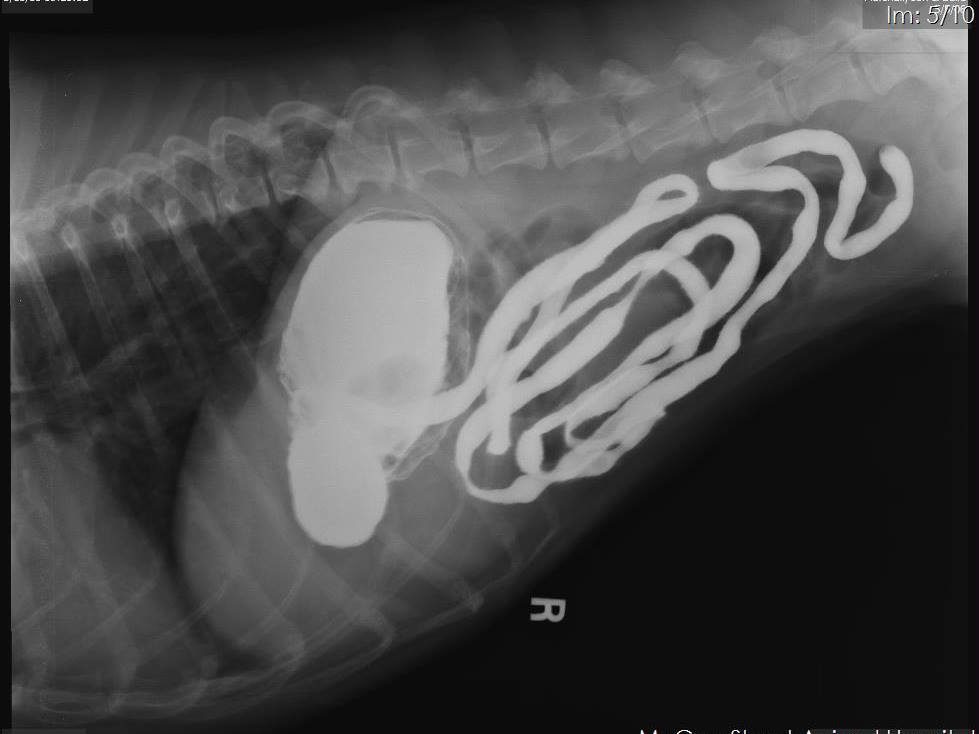

This is a case of a 10-year-old female spayed Boxer who has been anorexic intermittently for several weeks. Over the last week, the owner has had to syringe feed. Prior to onset, P was treated for cystitis, which resolved. Treatment for gastritis, including sucralfate, famotidine, and triamcinolone was only effective for a few days at a time. Chemistries on April 25 showed a slight elevation of lipase. CBC had very mild lymphopenia. Previous surveys' results were unremarkable for GI. Only 2 instances of vomiting have occurred during this time.

On the survey study you can see a soft tissue opacity in the stomach. However, be careful not to overinterpret this on a non-contrast image. Fluid in the stomach can often have this appearance and you can get a false impression of gastric wall thickening due to the air/fluid interface. However post adminstration of barium, we can now see a gastric mass causing a filling defect in the gastric wall on numerous images, and this confirms that what we saw on the survey images was a real finding. The contrast will surround the mass causing it to appear radiolucent and allowing us to define the margins. Primary differentials, particularly in this age and breed, would be neoplasia (lymphoma, adenocarcinomva).

Would you see this on ultrasound? Potentially, but it depends on your skill level in sonography, how much air is in the stomach, where in the stomach it is located, etc. So if you do not have access to ultrasound (or even if you do) or if you were unable to get a good view of the gastric wall this is a great study to do! Thank you to Dr. Greg Emmert (one of my vet school classmates!) and McGee Street Animal Hospital for this fascinating case!